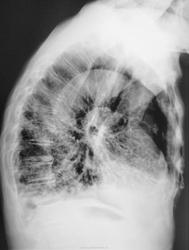

Это конечно шутка, а на самом деле здесь пневмония на фоне порока развития правого легкого. Справа внизу множественные ячейки. Ну и последствия травмы справа. Пневмония, думаю - дело временное.

Типа «сотовое лёгкое»? Нет? интересно, как оно выглядело до болезни?

Неоднозначно всё

Диф Ds поликистоз

бронхоэктазы

пневмосклероз с развитем сотового лёгкого?

Пневмония (возможно грибковая)

Я никак не могу разглядеть просвет среднедолевого бронха, проходим ли он в должной степени? Очень интересно было бы посмотреть контроль